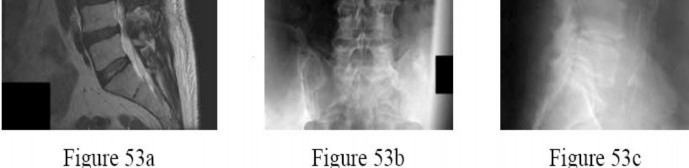

Question 53

A 55-year-old male with known renal cell carcinoma presents with progressive lower extremity weakness and bowel dysfunction.

Imaging reveals a destructive metastatic lesion at L3 causing mechanical collapse and severe canal stenosis. Operative decompression and stabilization are planned. What is the most critical preoperative step?

Explanation